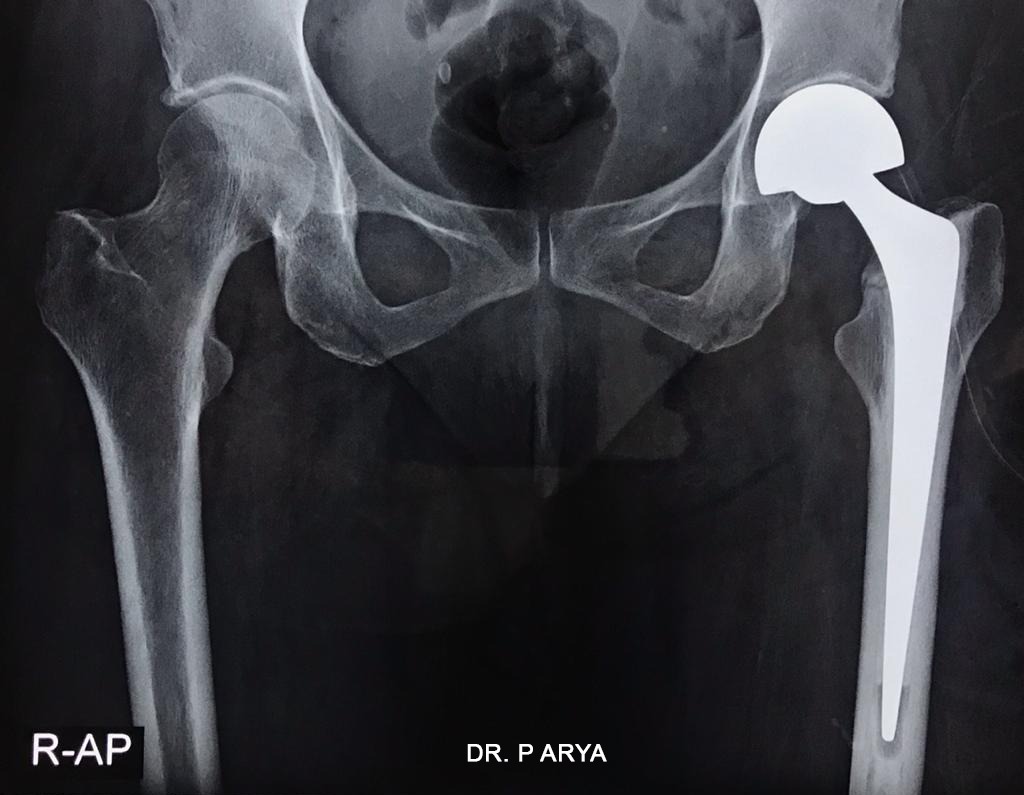

From www.drprashantarya.com

Best Orthopaedic Doctor Performs Hemi Hip Replacement Surgery Hip Replacement Blogs This blog post is here to guide you every step of the way. Read on to learn more about her history with hip pain, what she did to choose the best hip surgeon, and how she’s doing today. Sir john charnley's great innovation was to realise that low friction between the ball and socket of the hip implant was vital.. Hip Replacement Blogs.